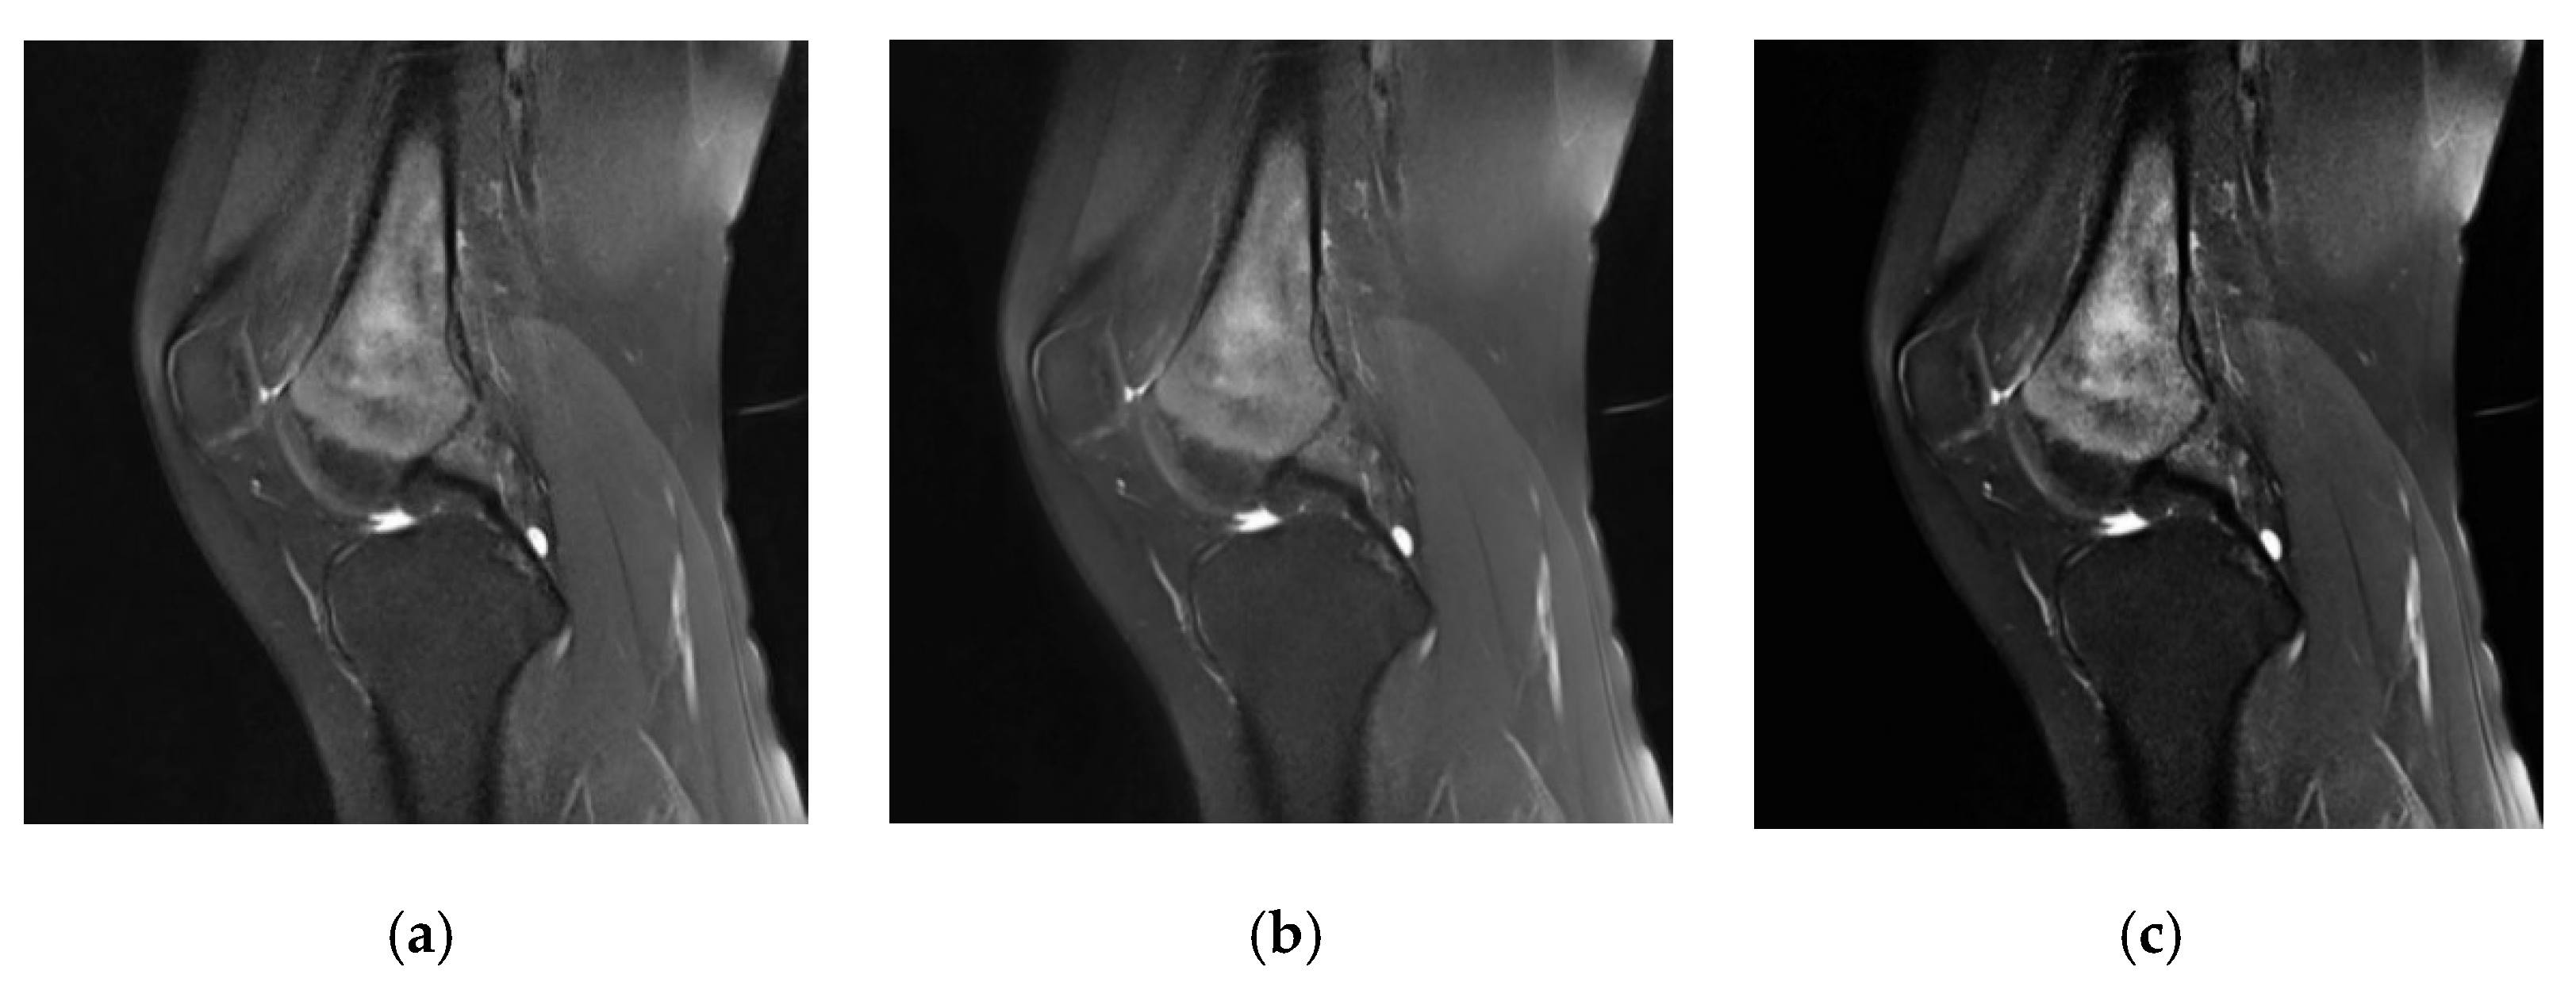

- This study proposes an auxiliary segmentation method of osteosarcoma in MRI images based on denoising and local enhancement, improving the accuracy and speed of segmentation and reducing resource consumption.

- We use the medical denoising model Eformer to remove noise and then localize and enhance the osteosarcoma region in MRI images. After preprocessing, the tumor region in the MRI image will be clearer and the boundary can be enhanced. Finally, an efficient and accurate network DFANet is used to segment osteosarcoma in MRI images.

3.2. Tumor Localization and Enhancement Methods